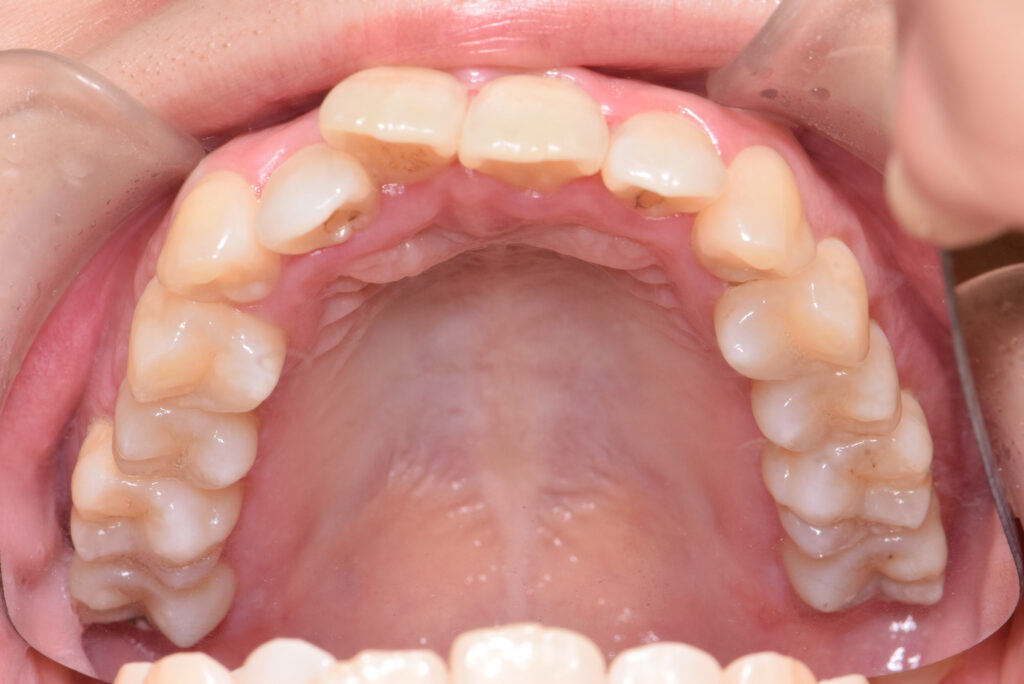

上顎

治療前